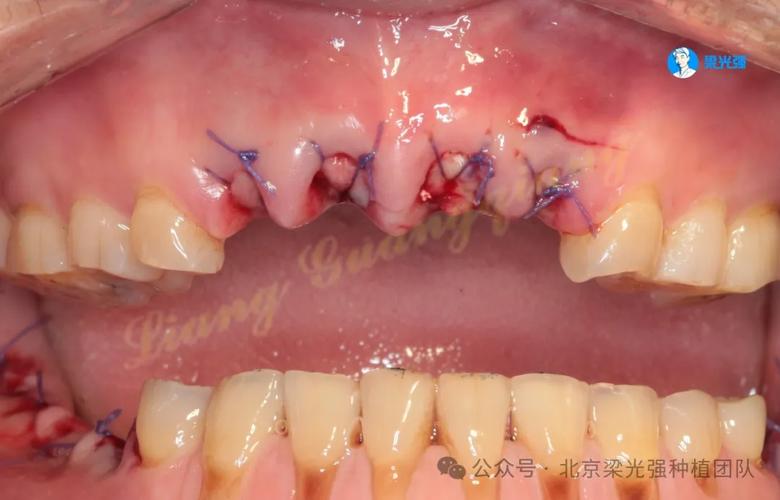

一旦怀疑种牙失败,需立即就医,医生会通过临床检查(如探诊、叩诊、松动度测试)和影像学检查(CBCT、X光片)明确失败原因,常见的处理方式包括:若为感染性失败(如种植体周围炎),需进行翻瓣清创、局部上药,并配合全身抗生素控制炎症;若骨结合失败(种植体与骨组织未融合),则需取出种植体,待炎症消退后评估骨量,必要时进行植骨,等待3-6个月骨愈合后再考虑二次种植;若为机械并发症(如种植体折断、基台松动),需根据折断位置选择取出修复或更换部件。

种牙失败的表现因失败阶段和原因而异,早期(术后3个月内)可能出现伤口长期不愈合、持续肿胀疼痛、种植体轻微晃动,甚至创口流脓;晚期(1年后)则多表现为牙龈反复红肿出血、种植体周围骨吸收、咬合时异响或松动,严重时种植体可能完全脱落,甚至引发颌骨感染或邻牙损伤,这些症状不仅影响口腔功能,还可能导致患者出现心理焦虑,对后续治疗产生抵触情绪。